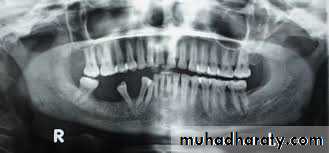

- Radiographically; bilateral multilocular cyst -like radiolucency, teeth seem to be floating within the tumor and may be malformed.- Treatment: surgical contouring is indicated when expansion is sever, leading to functional jaw or airway disturbances, or when the disease causes social problems in the older child. If possible, intervention is delayed until growth has completed.